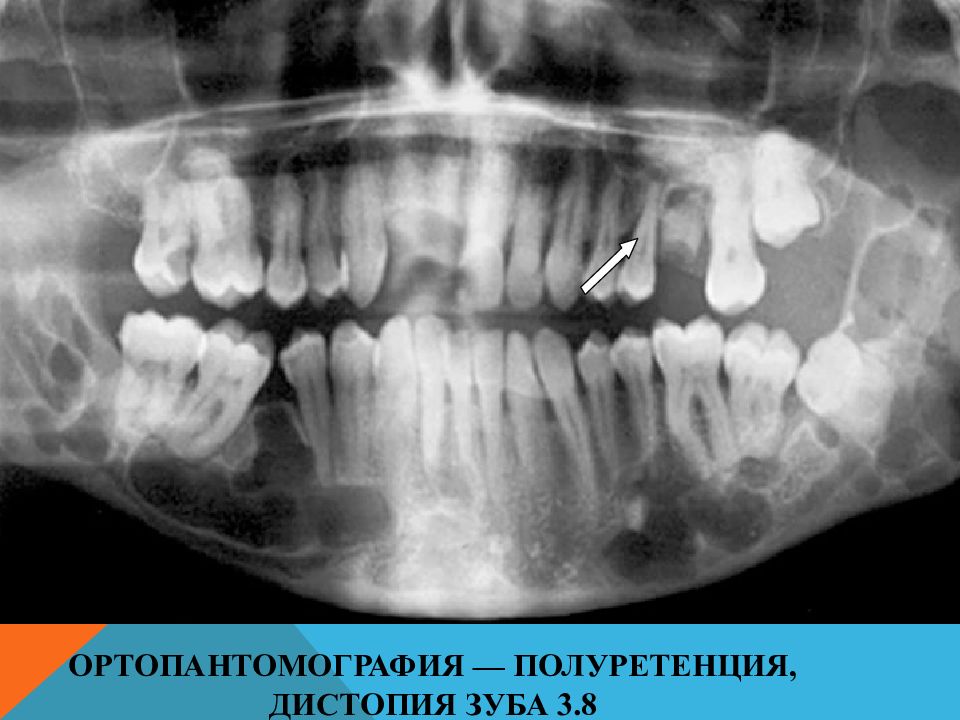

• Ортопантомография — полуретенция, дистопия зуба 3.8

Слайд 23: Ортопантомография — полуретенция, дистопия зуба 3.8